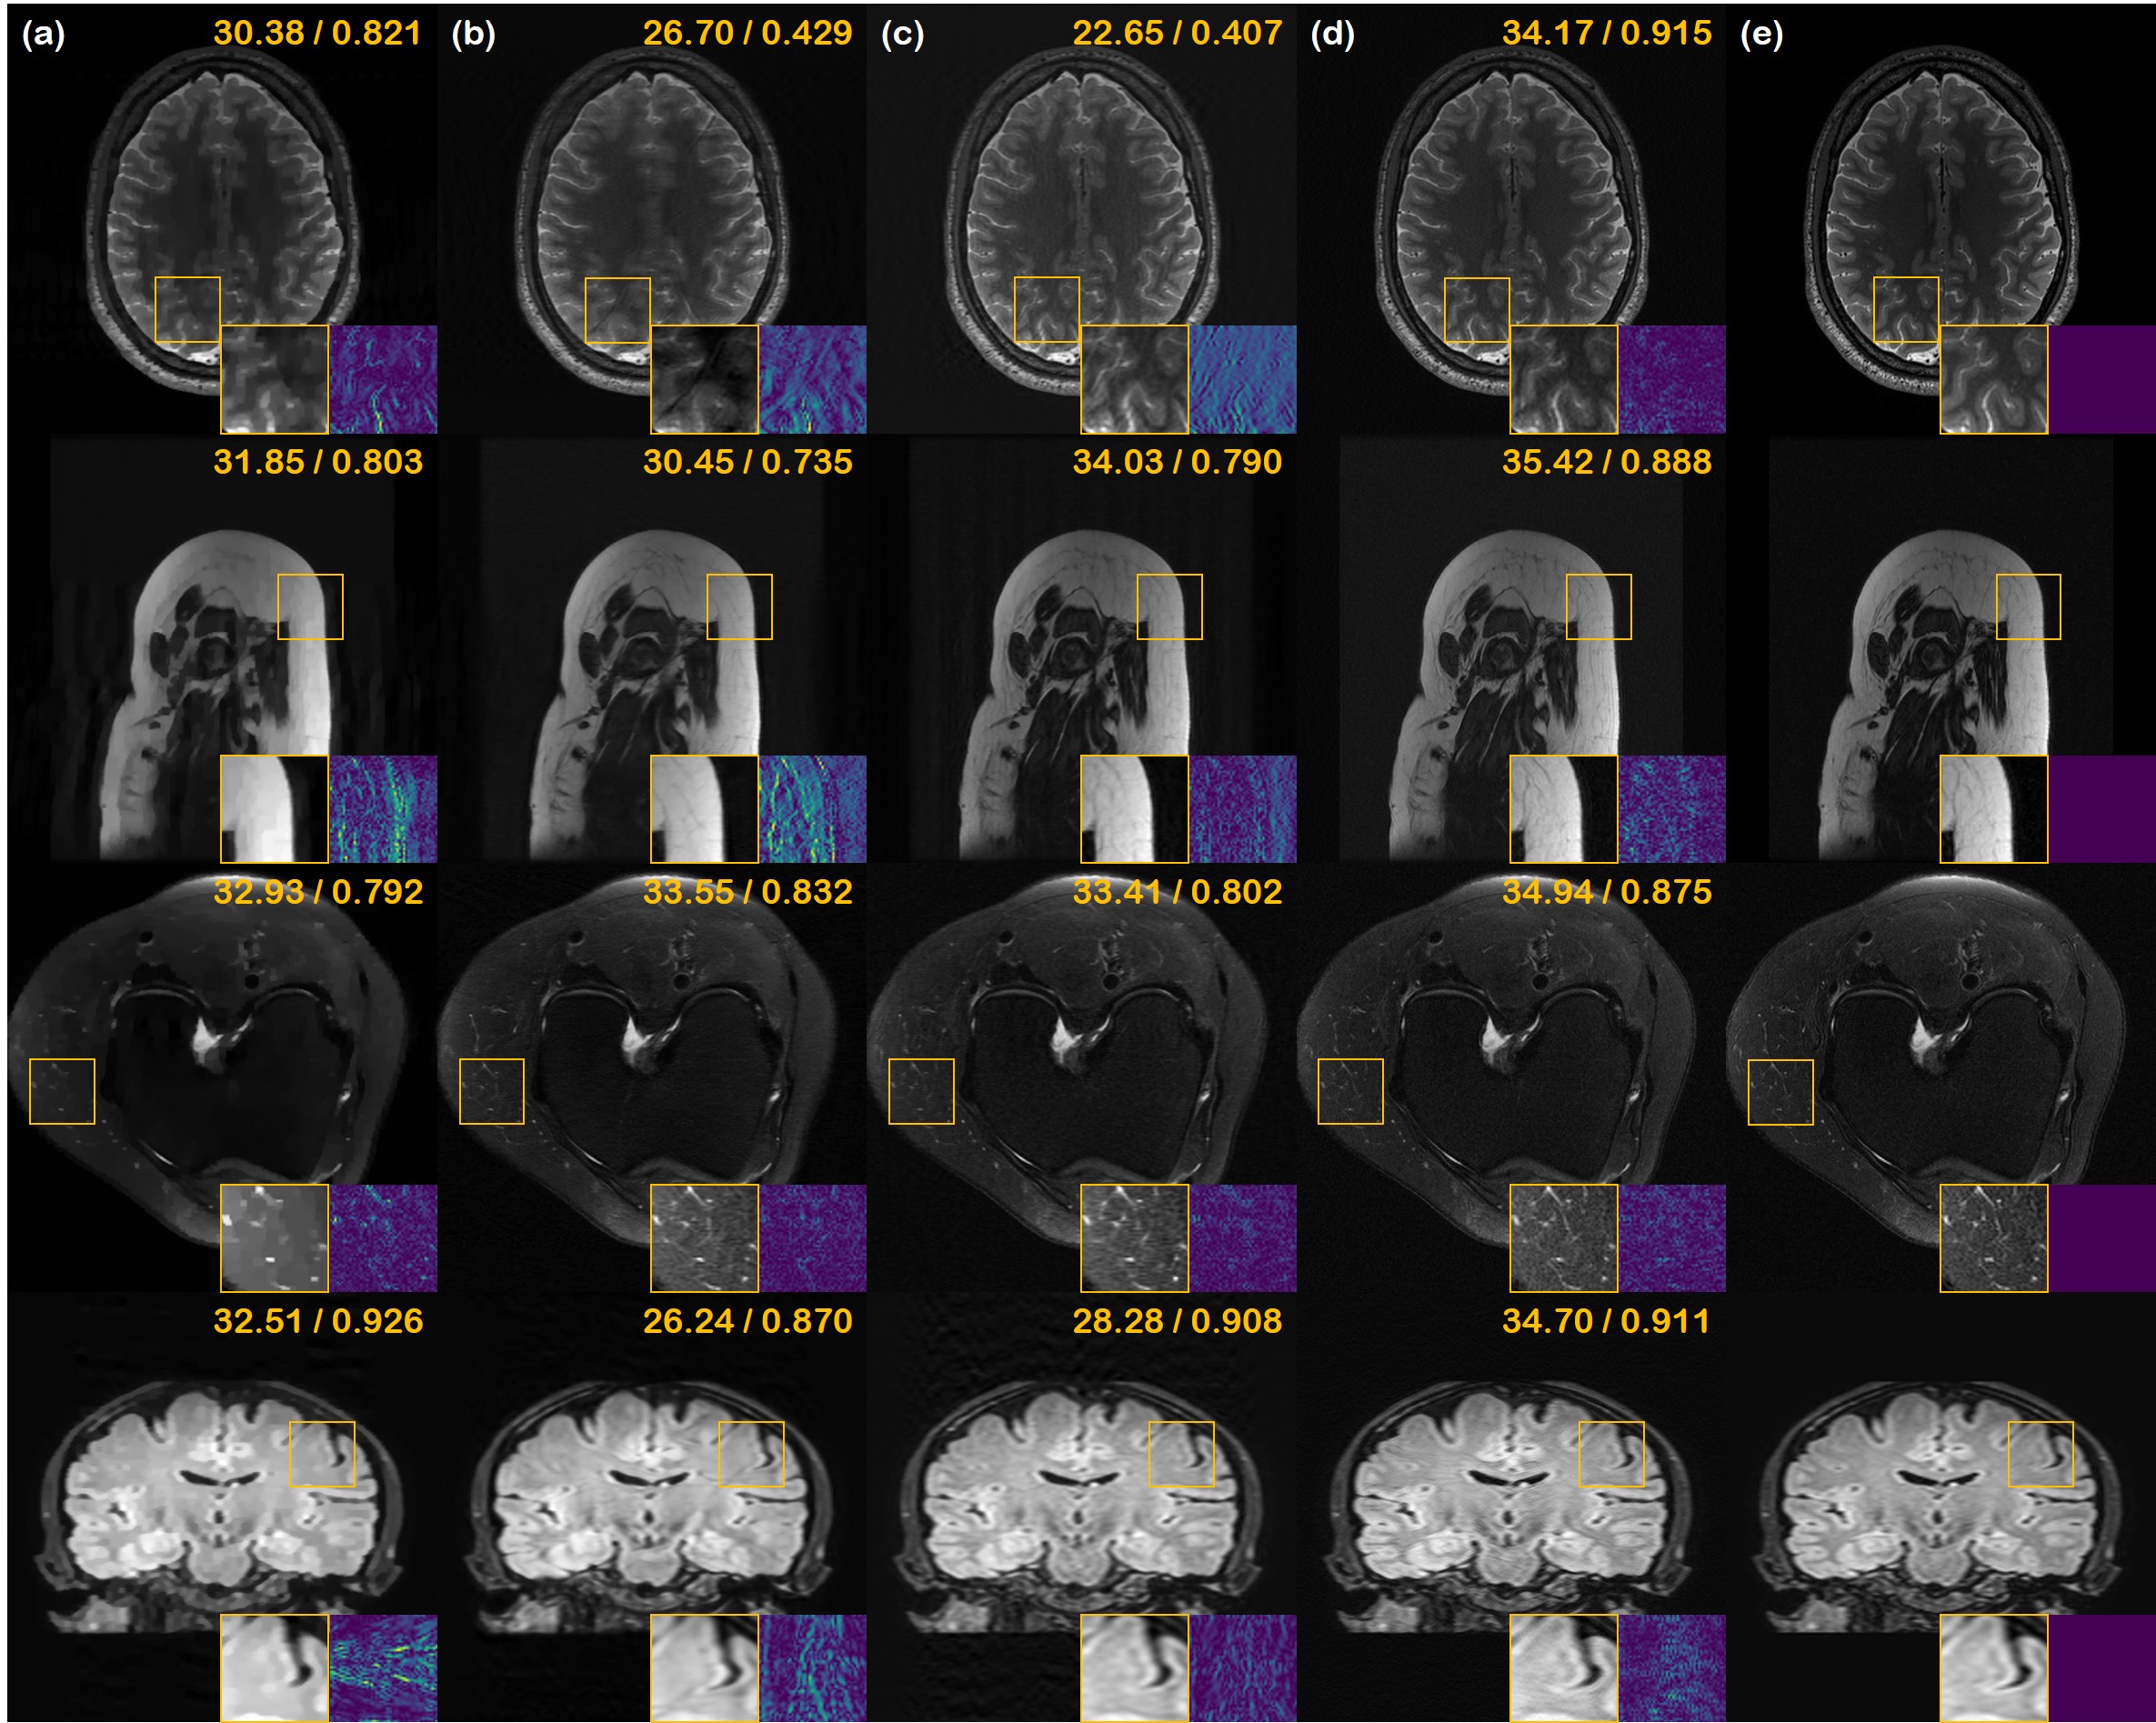

Refer to caption

Fig. 5: Multi-coil reconstruction results. (a) Sub-sampling mask used to generate under-sampled image, (b) TV, (c) supervised learning (U-Net), (d) E2E-varnet [59], (e) the proposed method, and (f) the ground truth. 1stst{}^{\text{st}} row: 2D ×\times8 Gaussian random sampling, 2ndnd{}^{\text{nd}} row: 1D ×\times4 Gaussian random sampling, 3rdrd{}^{\text{rd}} row: 1D ×\times 4 uniform random sampling, 4thth{}^{\text{th}} row: ×\times8 variable density poisson disk sampling. Green box: Zoom in version of the indicated yellow box, Blue box: Difference magnitude of the inset (in Viridis colormap). Yellow numbers in the upper right corner indiate PSNR [db], and SSIM, respectively.

We compare the results of PI reconstruction in Fig. 5. Consistent with the results from the prior sections, our method significantly outperforms other methods and is the only method that produces high fidelity reconstructions regardless of the sampling pattern. This can also be seen in Table 2, where we see that our method is on par with the SOTA E2E-varnet on 1D sampling patterns, while significantly outperforming all the methods in 2D sampling patterns.

The bias towards 1D sampling pattern for the deep-learning based method is much larger in the multi-coil case. This can be seen in the severe artifacts that can be seen in reconstructions via E2E-varnet (Fig. 5 (d)). We conjecture that this is because the sensitivity map estimation module of E2E-varnet fails dramatically with 2D sampling patterns, leading to horizontal streaking artifacts. Furthermore, although U-Net does not explicitly deal with sensitivity maps, the bias towards certain sampling patterns seems to be greater than in the single-coil experiments, showing reconstructions with heavy artifacts. On the other hand, our score-based method is agnostic to sampling patterns, clearly outperforming the comparison methods in all cases.

However, in the case of PI, we do observe some potential limitations of our method. Namely, since we consider stochastic samples from the conditional distribution for each coil, and then take the SSOS of the coil images at the last step to form the reconstruction, we recognize a small amount of averaging effect compared to single-coil reconstruction cases. Nevertheless, we emphasize that our method was not trained with multi-coil data, and is yet able to reconstruct PI data with state-of-the-art performance. Our method works with any arbitrary number of coils, without the need to calibrate sensitivity maps, thereby enabling a practical application to any type of scan.